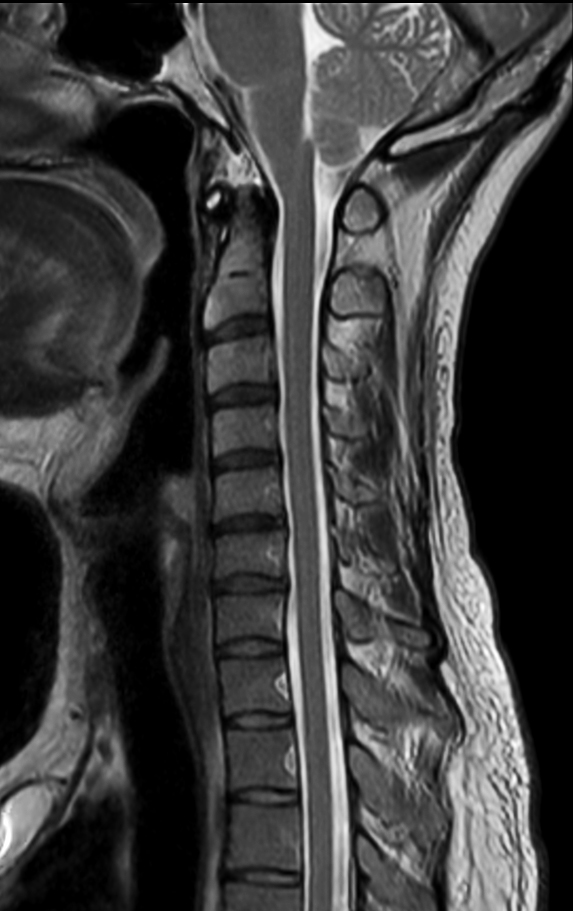

Sagittal T1w TSE

Sagittal T2w TSE